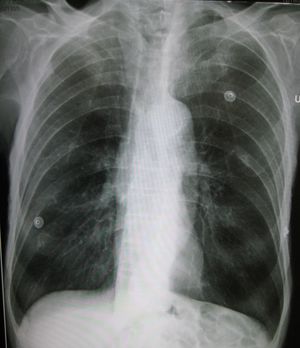

A lateral chest x-ray of a person with emphysema. Note the barrel chest and flat diaphragm. | |